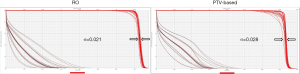

Figure 2 is the DVH for the same lung cancer case. The tables show all range and setup uncertainties for the CTV and spinal cord in the RO plan and the PTV-based plan. The solid lines are the DVHs for the nominal dose distribution which considers no uncertainties appeared. The dashed lines are the DVHs which are concerning different combination scenarios of range and setup uncertainties. By simply comparing the bandwidth in DVH at 50% of the targets compared to PTV-based optimization, we were able to quickly evaluate the plan robustness in defiance of uncertainties. In the figure, it is noticeable that the DVH bands in CTV are narrower for the RO than PTV-based plan. The CTV bandwidth were 0.76 Gy (RBE) in RO, and 3.78 Gy (RBE) in PTV-based optimization. Moreover, the falloff slope of the DVH bands in CTV was steeper, and the maximum dose of spinal cord was lower in the RO plan than PTV-based plan.

Besides from bandwidth comparison, we also used the following equation to calculate a sigma value (σ) so to quantify the distribution of DVH bandwidths in targets for each plan for robustness evaluation. If sigma value is smaller, it indicates the plans has less sensitivity to range and setup uncertainties.

σ=(

The outcome of sigma-value evaluation showed the RO plan was less sensitivity to the uncertainties by reducing sigma-value of 0.008 on average, and dose sparing on critical organs was not compromised.

Figure 3 and Figure 4 show the transverse dose distribution and DVH for one head-and-neck case. The dose distribution in the RO plan was insensitive to range and setup uncertainties compared to PTV-based plan. The DVH bands of target was narrower for the RO than PTV-based plan. The sigma value was also smaller which indicates the plan has less response to proton uncertainties. Both the head-and-neck and lung cases showed similar results.

For the other lung and head-and-neck cases both presented similar outcome. The sigma values of CTV were 0.007 [RO], and 0.014 [PTV-based] for the second lung case. For head-and-neck case, the sigma values were 0.018 [RO], and 0.021 [PTV-based]. No significant dose changes on critical organs were observed.